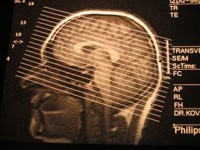

Ученым также удалось определить, что позитивное ожидание (плацебо-эффект) было связано с активацией цингуло-фронтальной коры головного мозга и подкорковых образований, а негативное (ноцебо-эффект) — с активностью гиппокампа и средней фронтальной коры. Исследователи считают, что эти результаты могут оказаться полезными при проведении клинических исследований, поскольку даже в рандомизированных плацебо-контролируемых исследованиях ожидание (с любым знаком) не учитывается.